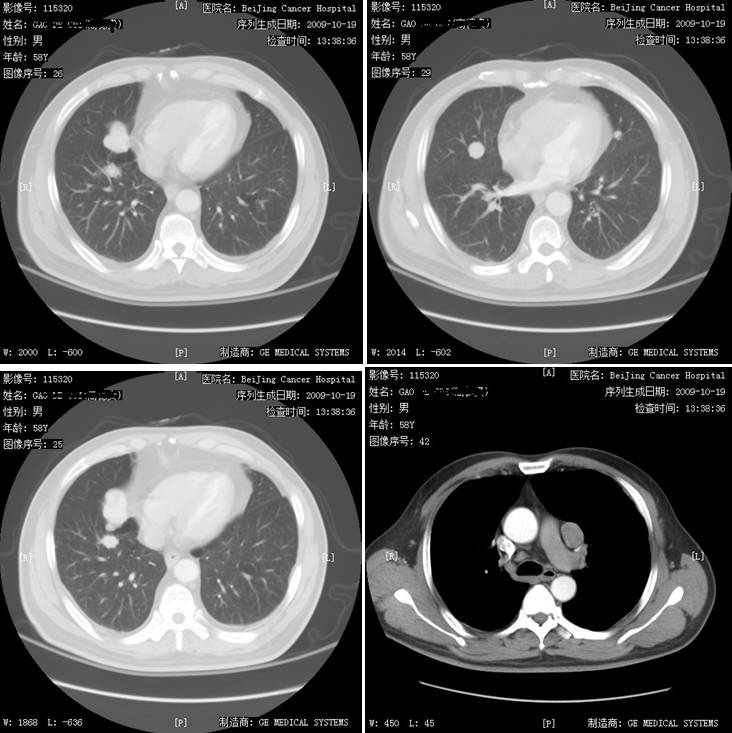

患者于1998年行右肾透明细胞癌术,术后行干扰素治疗1月余,2009年发现双肺多发占位,2009年11月开始口服培唑帕尼800 mg QD治疗。治疗2周期病灶缩小,治疗4周期达疾病稳定(SD),治疗期间出现肝损3度、血压升高、口腔黏膜炎、腹泻1~2度,培唑帕尼减量至600 mg口服治疗,疾病持续稳定。迄今患者术后已累计生存达18年,累计应用培唑帕尼治疗7年,生存状况良好。 姓名:高某 性别:男性 年龄:74岁 患者1998年行右肾透明细胞癌术,术后行干扰素治疗1月余。2009年因憋气/胸闷于石景山医院就诊。2009年10月19日,行胸部增强CT检查发现双肺多发结节,左肺门肿大淋巴结,纵隔小淋巴结,腹部改变,结合病史考虑转移,并建议进一步追查(图1)。2009年10月20日,行腹部CT发现腰3椎体骨转移(图2)。于2009年11月入北京肿瘤医院就诊。既往血糖升高。 图1 2009年10月19日胸部CT检查 双肺纹理走行顺畅,肺内透亮度均匀,双肺见多发大小不等结节,较大约28×23 mm(IMA26),未见肺内结节或斑片影;纵隔4组见小淋巴结,小于10 mm,左肺门见一肿大淋巴结,约26×21 mm(IMA42);锁骨上区及双腋下未见肿大来不及;双侧胸膜稍增厚,未见胸水征象;扫及发现双肺多发占位胸廓诸骨未见明确破坏征象;胃小弯可见一淋巴结,约1 cm(IMA13)。 图2 2009年10月20日腹部CT检查 口服培唑帕尼800mg QD治疗2周期复查病灶有缩小,治疗4周期疗效评价为SD(缩小)。治疗期间患者出现3度肝损伤(最高(ALT221iu/l)、血压升高、口腔黏膜炎、1~2度腹泻。考虑肝损害,予以减量至600mg Qd治疗,未再出现肝转氨酶显著升高,期间出现甲状腺功能减退,甲状腺素替代治疗未诉不适,每3个月复查,疗效评价均为SD。2017年4月21日,体格检查一般情况可,心肺未见异常。肿瘤复查未见增大。 2017年3月复查病灶大致同前,胃小弯淋巴结基本消失,腰3转移消失(图3)。 图3 2017年3月29日复查腹部CT:胃小弯淋巴结基本消失,腰3转移消失 肾透明细胞癌是最常见的肾脏肿瘤,约30%的患者在诊断时已经发生转移。目前晚期肾透明细胞癌的治疗已经是靶向治疗时代,其中主要以酪氨酸激酶抑制剂(TKI)为主,国内先后上市了索拉非尼、舒尼替尼、依维莫司、阿昔替尼、培唑帕尼等,其中,培唑帕尼与舒尼替尼是获得1类循证医学推荐的一线治疗用药,二者在既往的临床Ⅲ期研究中与安慰剂或干扰素相比,均显示了无进展生存(PFS)的获益,并得到了国内外众多指南的一致推荐。对于这两种药物临床如何选择呢?Robert J. Motzer等实施了一项全球多中心临床Ⅲ期随机对照研究,即COMPARZ研究。 该研究自2008年8月至2011年9月在北美、欧洲、澳大利亚和亚洲的14个国家(包括中国)共纳入1110例患者,以1︰1随机分组,分别给予培唑帕尼800 mg/d连续治疗(557例)或舒尼替尼4/2方案(4周50 mg/d,停药2周,553例)。结果显示,培唑帕尼的PFS非劣于舒尼替尼,研究者评审的中位PFS为:10.5个月和10.2个月。两组OS相当,培唑帕尼和舒尼替尼组分别达28.4个月和29.3个月,而培唑帕尼组的肿瘤应答率显著更高。与培唑帕尼组相比,舒尼替尼组患者有更高的疲劳(55%对63%)、手足综合征(29%对50%)和血小板减少症(41%对78%)发生率;而培唑帕尼组患者的丙氨酸氨基转移酶(ALT)水平升高率则高于舒尼替尼组(60%对43%)。在治疗前6个月14种健康相关生活质量较基线的比较中,培唑帕尼组有11种有显著优势,尤其是在疲劳或口腔、喉咙、手或足疼痛等方面,给患者带来了更高的生活质量和治疗满意度。该研究最终结果于2013年在《新英格兰医学杂志》发表,从而改写了晚期肾癌的临床治疗实践。 对于晚期肾癌的总体预后,靶向治疗的中位总生存时间为26-30个月左右,通常一线靶向药物治疗时间为1年左右,对于肺转移患者可以延长至2年左右,而该患者进入COMPARZ研究接受培唑帕尼治疗,持续接受培唑帕尼治疗迄今已累计治疗7年余,疗效评估持续维持缩小的SD,肿瘤获得良好的控制,生活质量良好,证实了培唑帕尼在临床实践中的良好疗效。也为肾透明细胞癌患者的临床一线靶向药物选择提供了有力的参考。 盛锡楠教授 副主任医师,副教授,硕士研究生导师,北京大学肿瘤医院肾癌黑色素瘤内科副主任。长期从事肿瘤内科临床和科研工作,擅长肾癌、膀胱癌、前列腺癌等泌尿肿瘤以及黑色素瘤的内科治疗。担任《中国肾癌诊治指南?2015版》执笔人,CSCO青委、CSCO肾癌专家委员会秘书,中国抗癌协会泌尿男生殖肿瘤专业委员会青委,北京抗癌协会泌尿男生殖肿瘤专业委员会委员兼秘书,CGOS分子靶向分委会常委。病例摘要